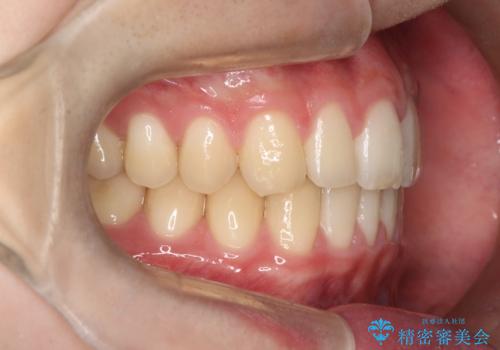

【ワイヤー矯正】すきっ歯を治したい

- 主訴:上の前歯のすきっ歯を治したい。

今回のような空隙歯列に対したは、マウスピース矯正・ワイヤー矯正どちらの方法でも矯正治療可能と説明し、ワイヤー矯正を希望されました。

上顎中切歯間の隙間の他にもフロスが抵抗なく入るスペースが上顎は数か所ありました。スペースを閉じ下顎の歯列弓との調和をとるためIPRを行いました。

下顎の舌側傾斜気味の前歯も唇側へ歯軸傾斜させています。

矯正期間:1年2か月